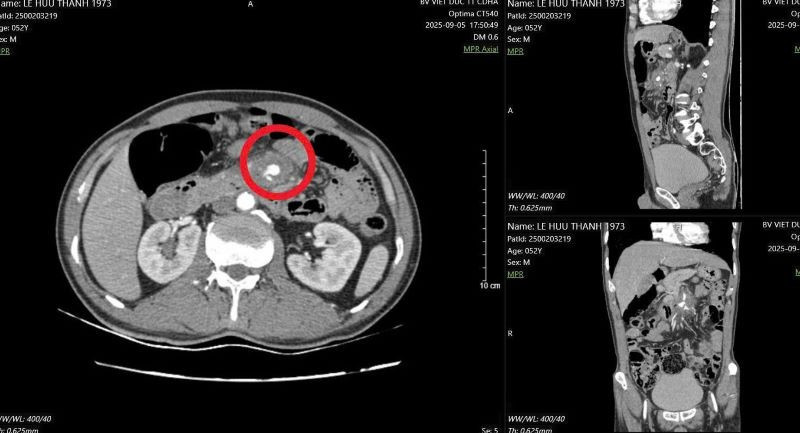

Qua thăm khám và chụp chiếu, các bác sĩ phát hiện trong cơ thể người bệnh có một chiếc tăm tre đã đi sâu xuống phần tá tràng – tức là đoạn đầu của ruột non, nối tiếp sau dạ dày.

Chiếc tăm này không chỉ dừng lại ở đó mà đã đâm xuyên qua thành ruột, tạo ra một ổ viêm nhiễm, tụ mủ (gọi là áp xe) có kích thước khoảng 4 cm trong phần mô mỡ và mạch máu bao quanh ruột non.

Hình ảnh đoạn D3 tá tràng tổn thương, cạnh động mạch mạc treo tràng trên - Ảnh BVCC

Nguy hiểm hơn, đầu tăm tiếp tục đâm vào một trong những mạch máu lớn nhất trong ổ bụng – động mạch mạc treo tràng trên, là nơi đưa máu nuôi phần lớn ruột non. Tổn thương này đã khiến thành mạch máu bị phồng lên giả tạo (gọi là “giả phình mạch”), nếu không được phát hiện và xử trí kịp thời có thể gây vỡ mạch, chảy máu ồ ạt trong ổ bụng, đe dọa tính mạng.